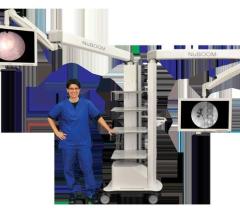

CompView Medical (CVM) introduced an all-in-one equipment manager, visualization and ergonomic boom system — the NuCart.